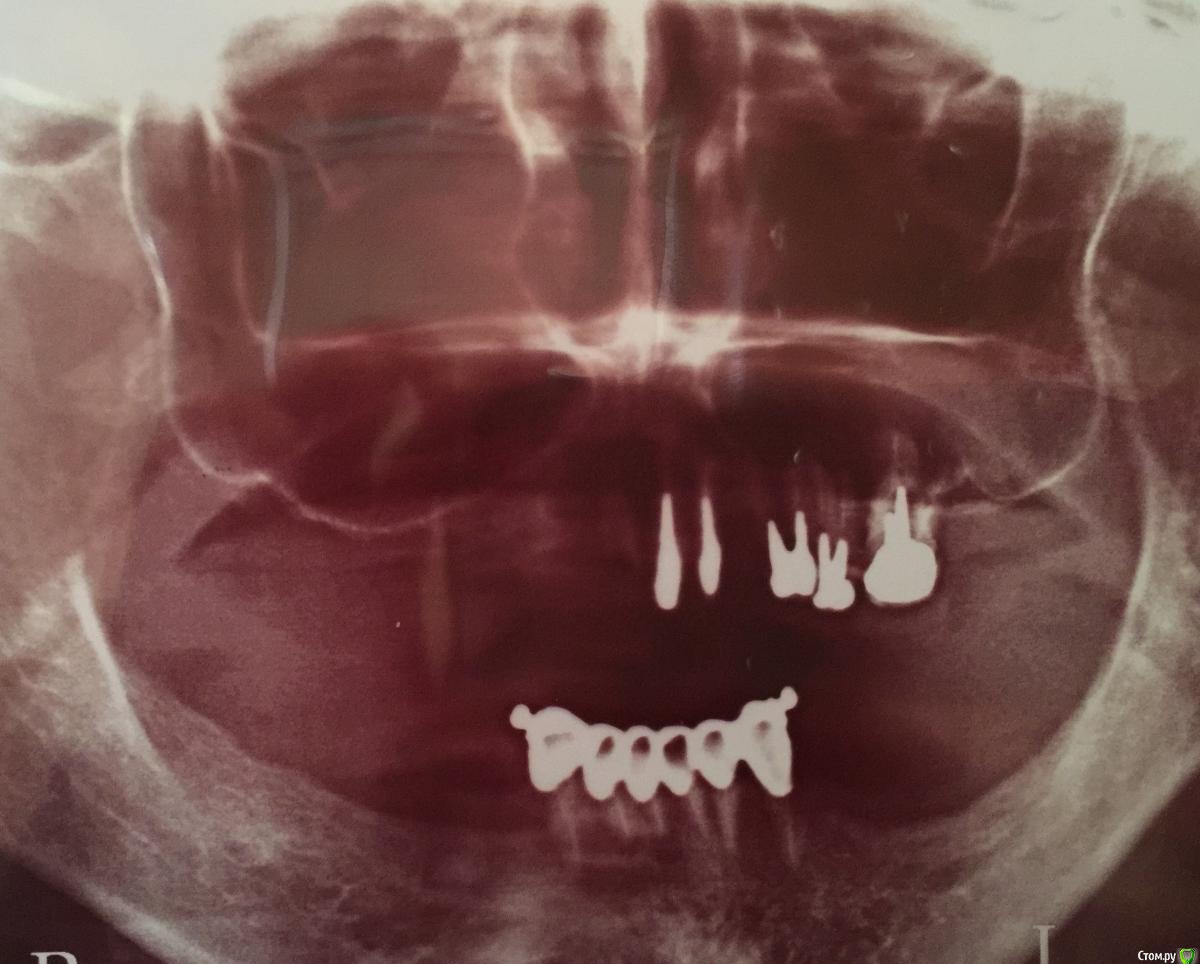

Ольга Сом Опубликовано 30 сентября, 2015 Поделиться Опубликовано 30 сентября, 2015 Добрый день! Посоветуйте пожалуйста план лечения (протезирования) на имплантах в таком запущеном случае.Хочется несъемные зубы. Основательно, что бы лет на 20 хватило Заранее спасибо Снимки прилагаются Ссылка на комментарий

Bier Опубликовано 11 октября, 2015 Поделиться Опубликовано 11 октября, 2015 Все зубы в итоге нужно будет удалить, по 6 имплантатов внизу и наверху Ссылка на комментарий